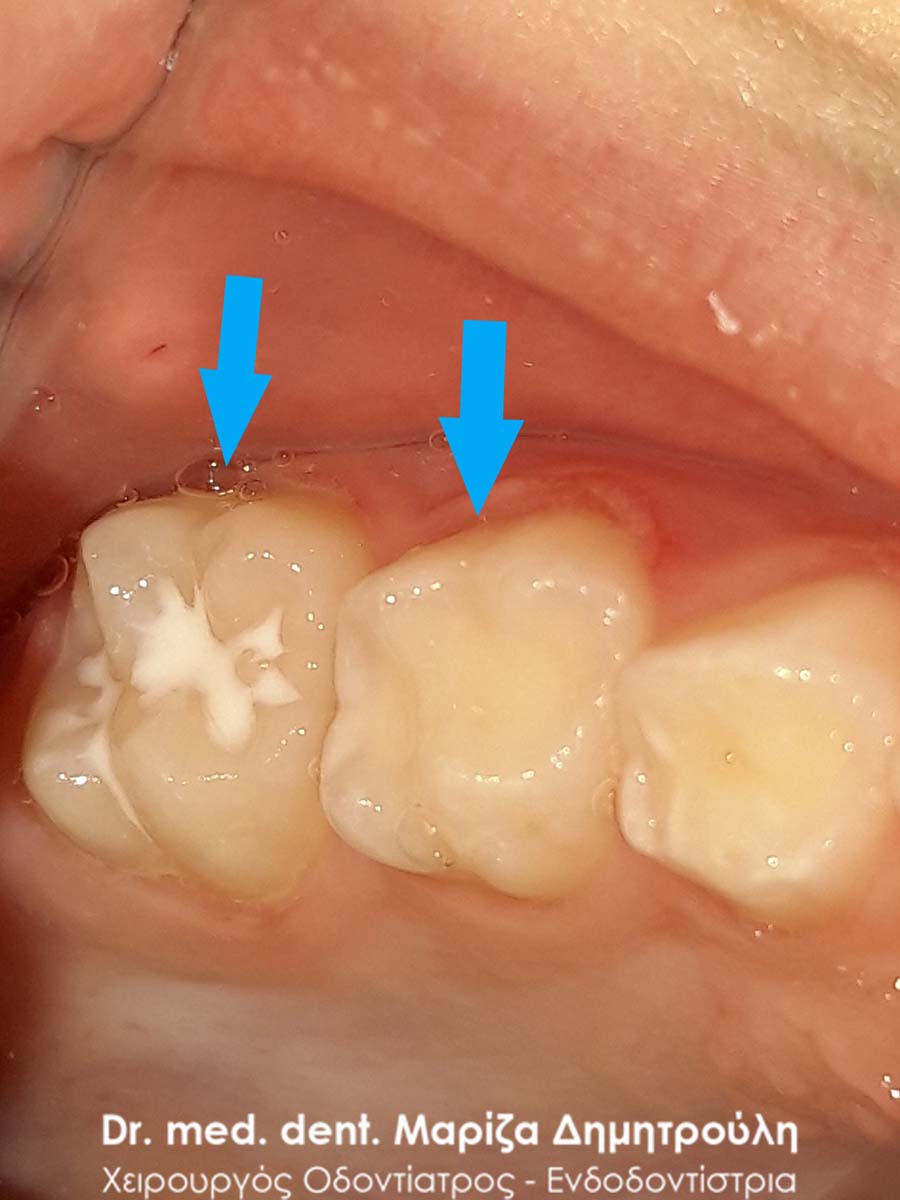

Το μικρό αγόρι επισκέφτηκε για πρώτη φορά οδοντίατρο. Η οδοντίατρος που εξέτασε τα παιδιά στο σχολείο σημείωσε οτι υπήρχαν κάποιες τερηδονικές κοιλότητες, οι οποίες θα έπρεπε να αποκατασταθούν. Στο συγκεκριμένο ασθενή πραγματοποιήθηκαν τόσο λευκά σφραγίσματα στα δόντια που ήταν τερηδονισμένα όσο και προληπτικές καλύψεις στις μασητικές επιφάνειες των μόνιμων γομφίων για την προστασία τους από τυχόν μελλοντική τερηδονική δραστηριότητα. Τα sealants στην προκειμένη περίπτωση ήταν για έναν παραπάνω λόγο αναγκαία, εφόσον το παιδί είχε ήδη μεσαίου βαθμού τερηδονική δραστηριότητα.

Επίσης στην πρόσθια περιοχή της άνω γνάθου παρατηρήθηκε ένα μικρό συρίγγιο στην περιοχή του πρώτου αριστερού νεογιλού γομφίου, ο οποίος είχε έντονη κινητικότητα χωρίς όμως να “πέφτει”. Στην περίπτωση αυτή ήταν απαραίτητη η εξαγωγή του νεογιλού δοντιού, γιατί το παιδί είχε το συρίγγιο τουλάχιστον τις τελευταίες 3 εβδομάδες (σύμφωνα πάντα με τα λεγόμενα της μητέρας). Με την εξαγωγή του δοντιού το συρίγγιο υποχώρησε τις επόμενες μέρες και το παιδί ανακουφίστηκε.

Συρίγγιο στην περιοχή του πρώτου νεογιλού τομέα

ΠΡΙΝ

ΜΕΤΑ – Sealant μόνιμου δοντιού

ΜΕΤΑ – Σφράγισμα νεογιλού δοντιού και sealant μόνιμου δοντιού